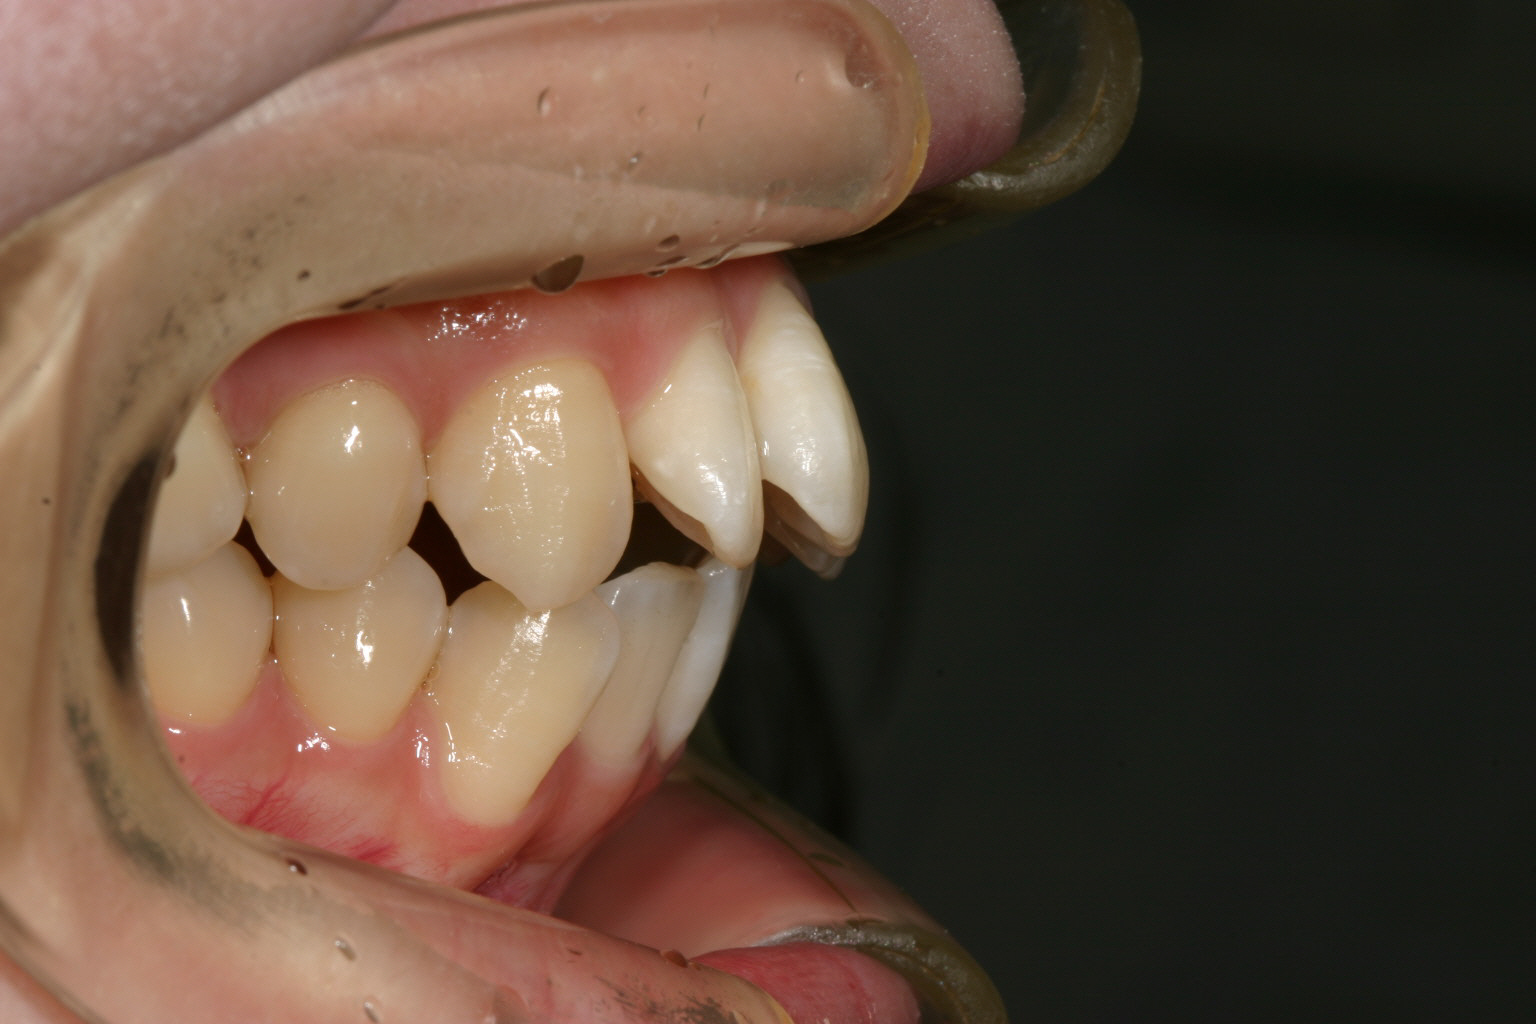

前歯のねじれと出っ歯を治したい。

前歯が飛び出てねじれています。

少し出っ歯が目立ちます。